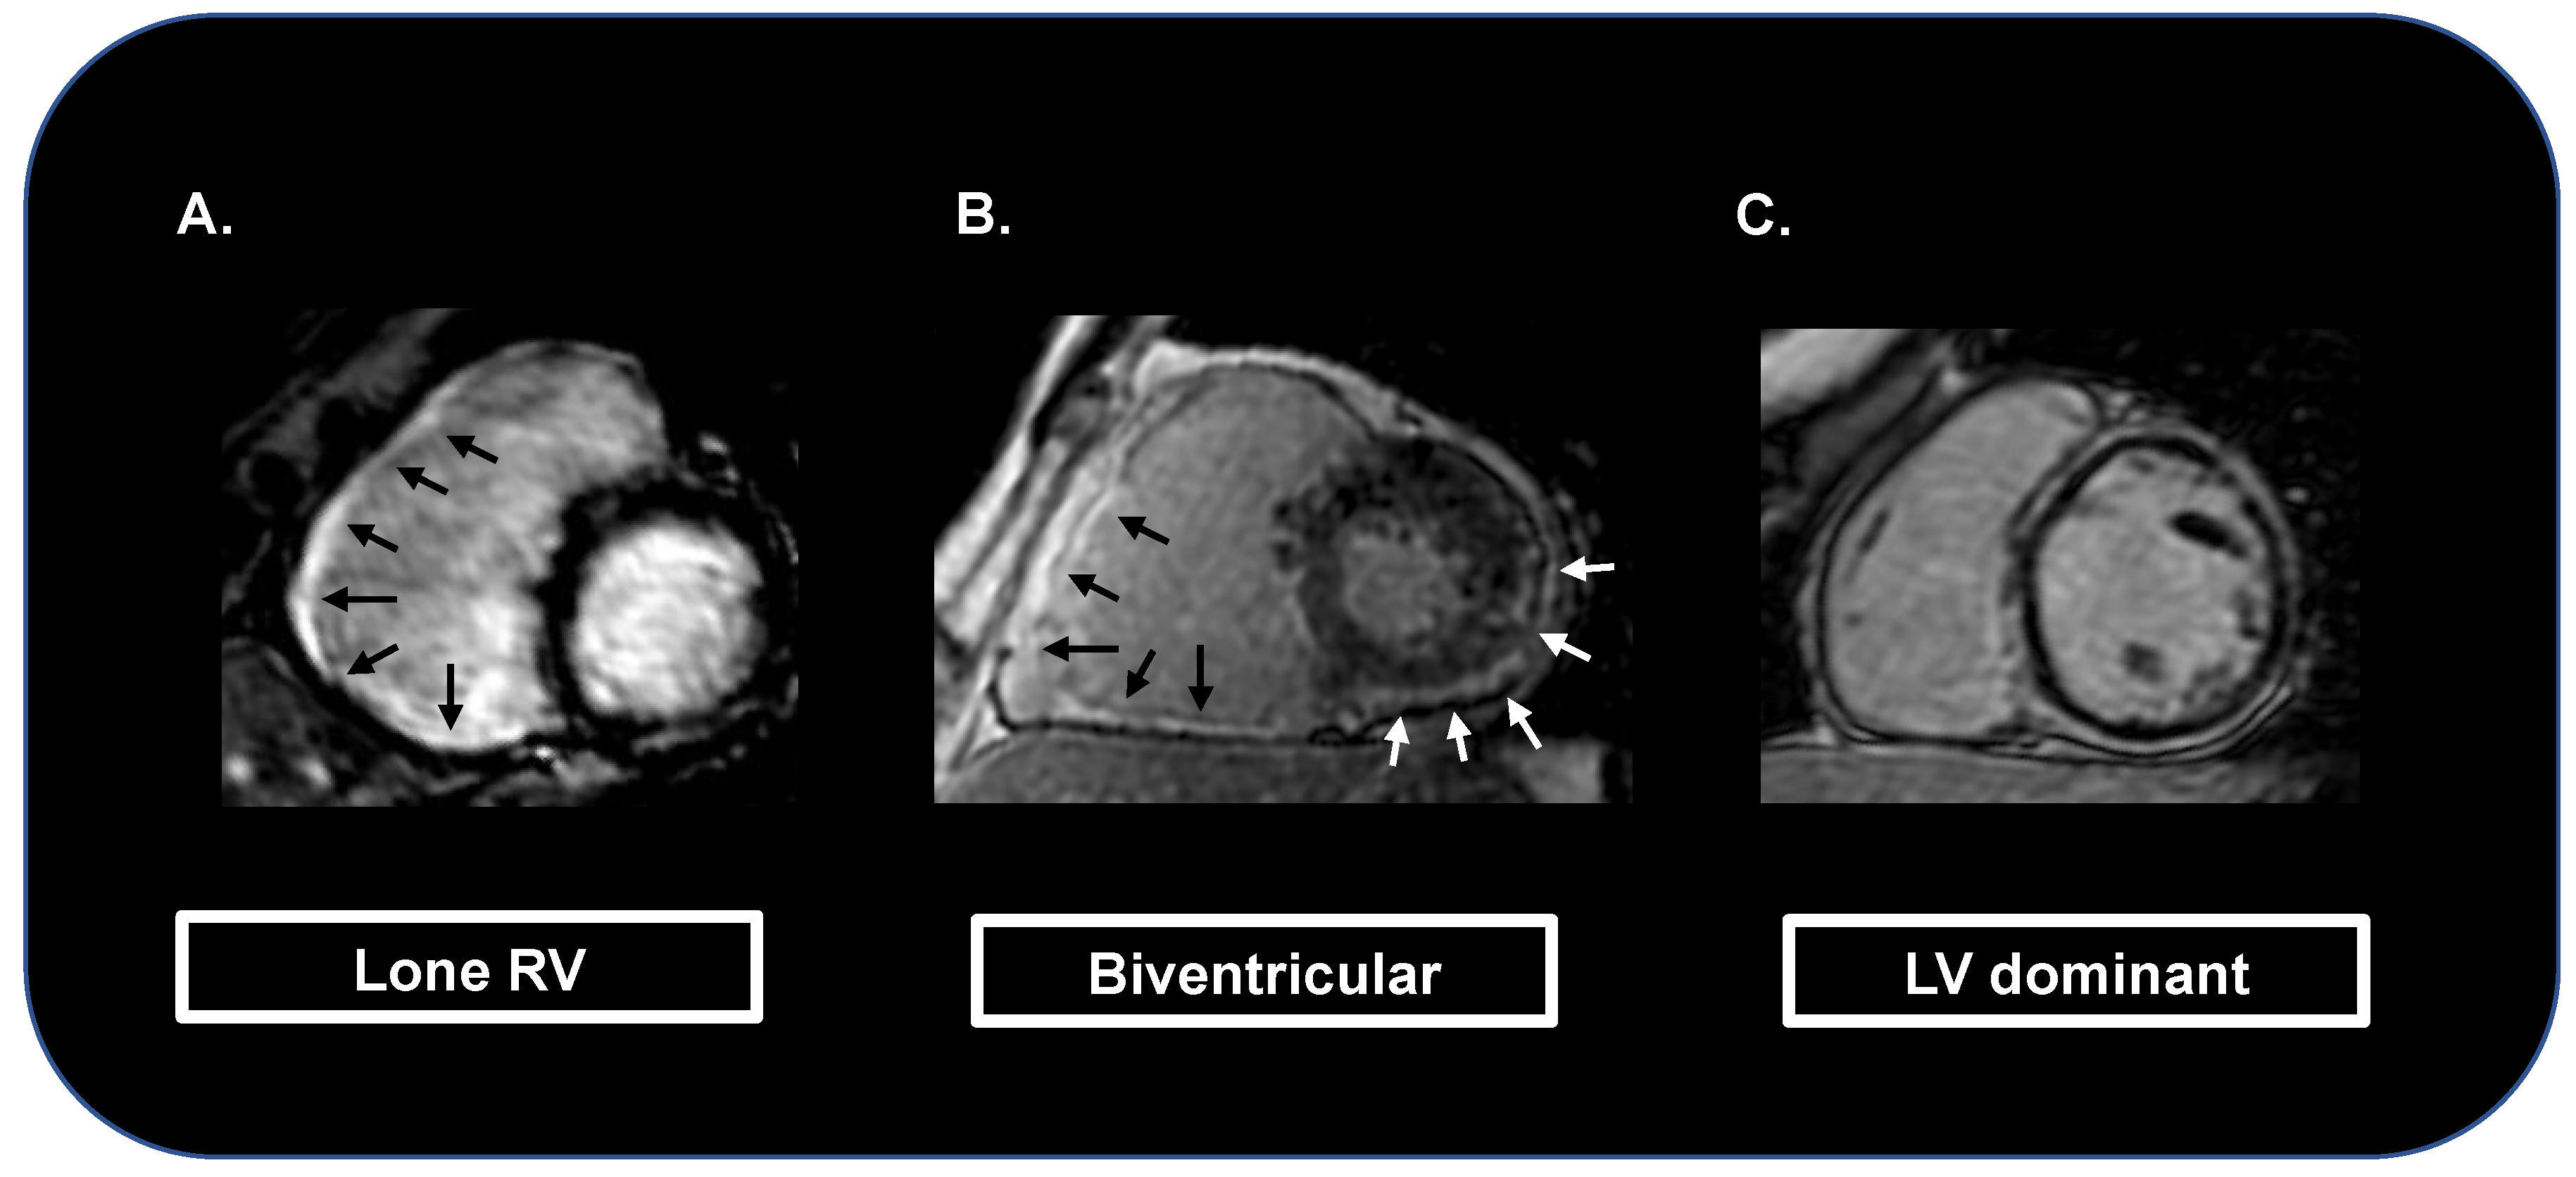

- Aquaro, G.D.; De Luca, A.; Cappelletto, C.; Raimondi, F.; Bianco, F.; Botto, N.; Lesizza, P.; Grigoratos, C.; Minati, M.; Dell’Omodarme, M.; et al. Prognostic Value of Magnetic Resonance Phenotype in Patients with Arrhythmogenic Right Ventricular Cardiomyopathy. J. Am. Coll. Cardiol. 2020, 75, 2753–2765. [Google Scholar] [CrossRef]